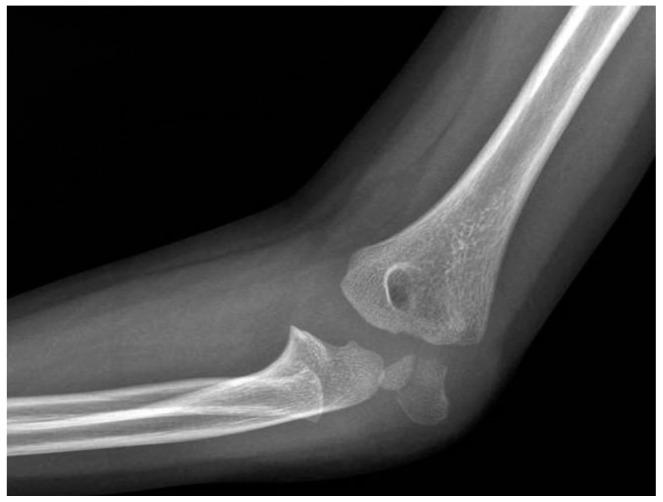

Fractures of the lateral condyle of the humerus are one of the most common fractures in children, accounting for between 10% and 20% of fractures involving the elbow, with a peak incidence at 6 years of age. Treatment is often surgical for displaced fractures > 2 mm, according to Milch and Jakob classification. There is no consensus in the literature about the appropriate surgical management of these fractures. : The aim of this study is to describe, propose, and evaluate outcomes and complications of the surgical technique of reduction and osteosynthesis using trans-bone suture with resorbable threads. : Patients with lateral condyle fractures treated with this surgical technique from 2015 to 2019 were included in this retrospective study, with a minimum follow-up of 24 months. For clinical and functional assessment of the elbow, Mayo Elbow Scores were recorded; we assessed the time of fracture healing, carrying angles, and Baumann angle of the affected limb compared to the healthy contralateral elbow for radiographic data. Complications have also been described. : We achieved satisfactory results; 36 patients with lateral condyle fractures were included in this study. Radiological healing was achieved in all cases. There was only one complication. No cases required additional surgical procedures. Almost all patients achieved a complete flexion of 110 degrees or more and complete extension. : This surgical technique has good functional outcomes and fracture healing, a lower incidence of complications when compared to other surgical techniques, and no mechanical failure with good clinical and radiological results.

肱骨外侧髁骨折是儿童最常见的骨折之一,占肘部骨折的10%至20%,发病高峰年龄为6岁。根据米尔奇(Milch)和雅各布(Jakob)分类法,对于移位超过2毫米的骨折,治疗通常采用手术治疗。关于这些骨折的适当手术管理,文献中尚无共识。本研究的目的是描述、提出并评估使用可吸收线经骨缝合进行复位和骨固定手术技术的结果及并发症。本回顾性研究纳入了2015年至2019年采用该手术技术治疗的外侧髁骨折患者,最小随访时间为24个月。对于肘部的临床和功能评估,记录梅奥肘关节评分;对于影像学数据,我们评估了骨折愈合时间、携带角以及患侧肢体与健康对侧肘部相比的鲍曼角。还描述了并发症情况。我们取得了满意的结果;本研究纳入了36例外侧髁骨折患者。所有病例均实现了放射学愈合。仅出现1例并发症。无需进行额外的手术。几乎所有患者均实现了110度或更大角度的完全屈曲和完全伸展。该手术技术具有良好的功能结果和骨折愈合情况,与其他手术技术相比并发症发生率较低,且无机械故障,临床和放射学结果良好。